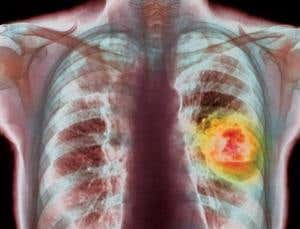

Lung cancer in people who have never smoked is a very different disease (Image: Simon Fraser/ Science Photo Library)